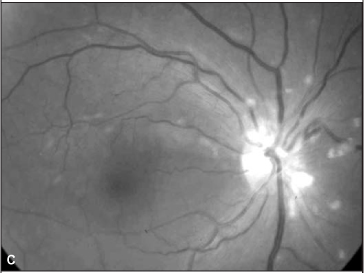

Ao exame oftalmológico observou-se acuidade visual corrigida de 20/200 no olho direito e de 20/20 no olho esquerdo. À oftalmoscopia indireta evidenciou-se no olho direito: retina colada, hiperemia do disco óptico com múltiplos exsudatos algodonosos circunjacentes, discreta tortuosidade e dilatação venosa, esparsas hemorragias retinianas e exsudatos algodonosos no pólo posterior e média periferia (Figura 1). O olho esquerdo apresentava alguns exsudatos algodonosos, porém sem outras alterações. À tonometria, medida com tonômetro de Goldman, registraram-se valores de 12 mmHg em ambos os olhos. A biomicroscopia e a motilidade ocular se mostraram normais em ambos os olhos.

No caso aqui relatado, descreve-se a retinopatia por interferon peguilado, que difere da grande maioria dos casos relatados de retinopatia associada ao uso de interferon alfa ou beta convencionais. Chama também a atenção, neste caso, a manifestação ocular tardia, pois o paciente vinha fazendo uso da medicação há aproximadamente dois anos antes de desenvolver sintomas. A baixa da acuidade visual do olho direito ocorreu, provavelmente, por má perfusão capilar retiniana na região macular, evidenciada por alguns exsudatos algodonosos no pólo posterior, e também pelo acometimento do nervo óptico: a retinografia colorida revela hiperemia de disco óptico e borramento do seu bordo superior. Há pubicações que relatam acometimento do nervo óptico associado ao quadro de retinopatia(10). Tanto as alterações de pólo posterior quanto do nervo óptico não são evidenciadas nas retinografias tomadas após a suspensão da medicação.